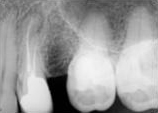

antes depois